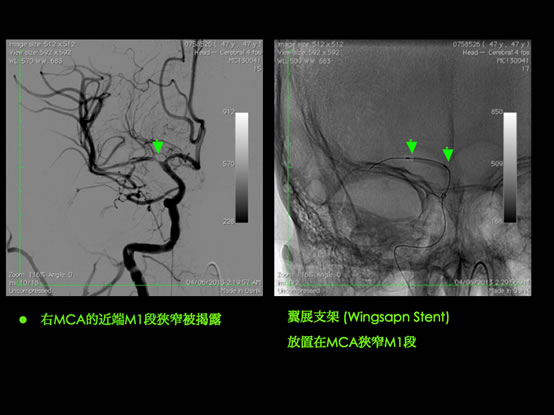

HKBSSP 推出治療急性缺血性中風的嶄新「黃金八小時」概念: 腦內血管介入的微創手術(機械式吸取血栓術),正正填補了靜脈注入溶血劑rtPA的黃金3至4.5小時治療方案的不足。 病人可於中風症狀出現後的八小時內接受腦內血管介入的微創手術(機械式吸取血栓術),把血管再次灌通。就像心臟的通波仔微創手術, 專攻腦內血管治療的神經外科醫生會從腹股溝把微型導管放入腦血管,擊碎及吸走腦內血栓,把血管再次灌通, 令腦細胞重獲生機。腦內血管微創手術在大腦血管造影導引下,不但能於大腦栓塞的確實位置進行治療,高度準確地移除血栓。 有時候,如果神經外科醫生發港現病變和狹窄的腦動脈, 而其是造成中風的主要原因,醫生植入柔軟的金屬支架, 將大腦動脈重建。